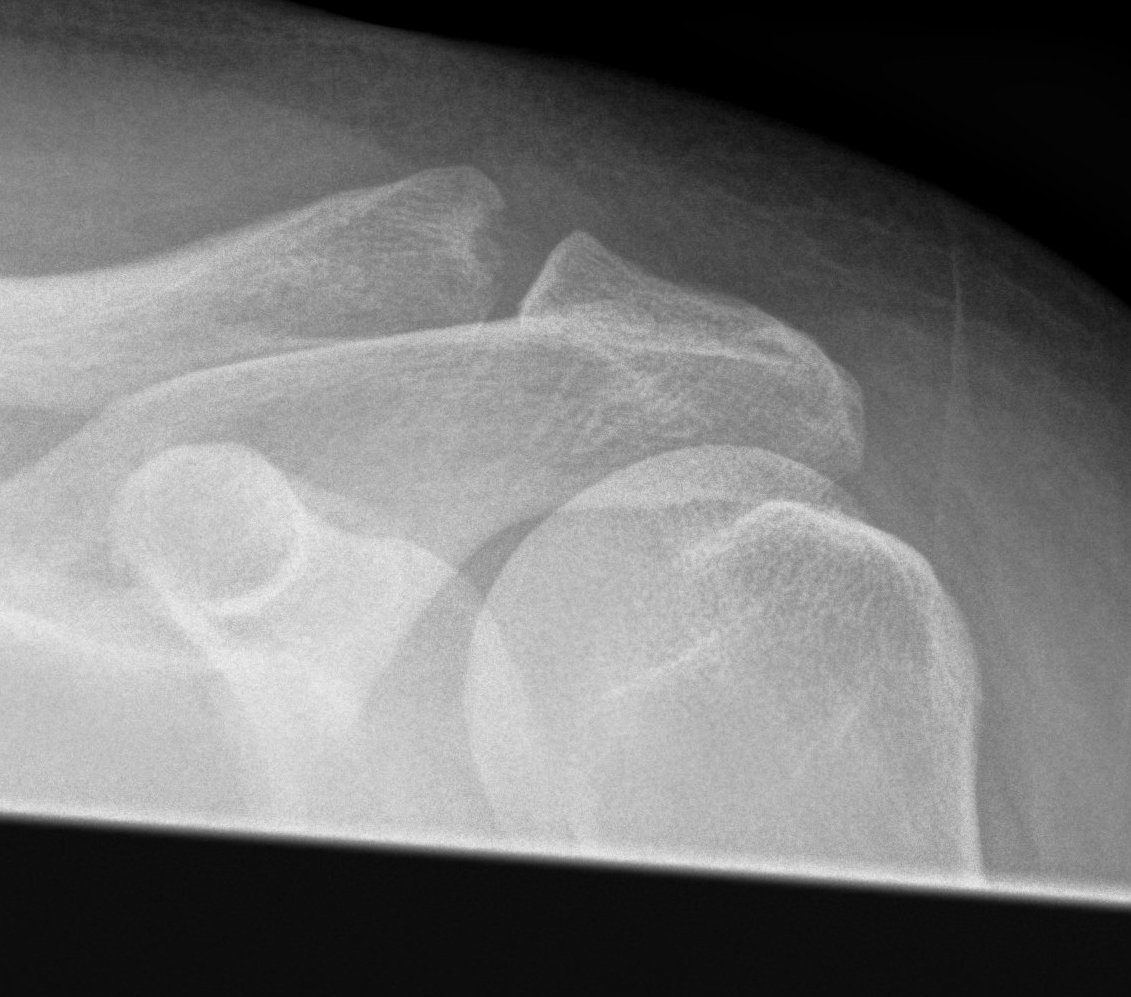

Acromioclavicular joint osteolysis

Osteolysis

Area of distal clavicle resorption

- due to repetitive microtrauma

- typically weight lifters or manual workers